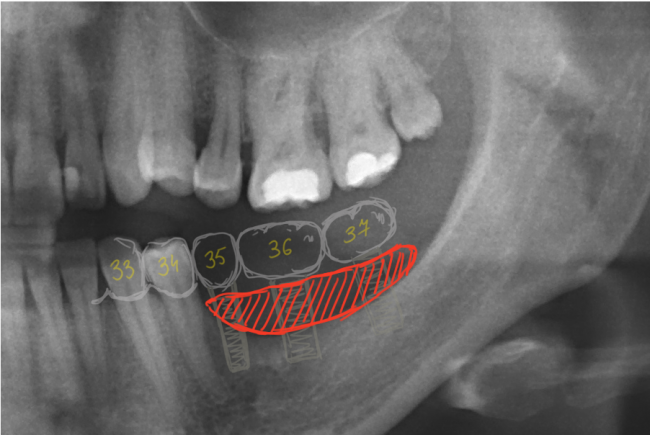

По данной схеме уже видно, какого объема костной ткани нам не хватает. В дополнение к снимкам, в клинике мы часто делаем диагностические модели, на которых восстанавливаем зубы и отсутствующую костную ткань с помощью воска — это т. н. WaxUp. Так мы моделируем и можем увидеть конечный результат нашей работы и планировать операцию. К сожалению, WaxUp показать не могу (поленился сфотографировать, лошара ;-)).

Это вполне осуществимо с помощью операции остеопластики, «наращивания костной ткани».

В общих чертах, схема будущей операции выглядит так:

- Способ проведения операции — аутотрансплантация костного блока из ретромолярной области и ветви нижней челюсти с последующей фиксацией винтами. Это наиболее предсказуемый метод вертикальной остеопластики, дающий максимум положительных результатов. Ни один метод с использованием ксенотрансплантатов (Bioss, Cerabone, Easygraft и т. д.) такой статистики не дает.

- Под блоком, вероятно, будет небольшое пустое пространство вследствие неплотного соответствия поверхностей. Его заполняем аутокостной стружкой, взятой из того же участка, что и блок. В этом случае использование барьерной мембраны (BioGide, Jacon и т. д.) ОБЯЗАТЕЛЬНО.

- Пересаженный костный блок также подвержен атрофии — за 3 месяца мы потеряем, порядка 20-30% от первоначального объема. Поэтому блок берется с запасом, учитывающим возможную атрофию. НО есть один нюанс — это верхние выдвинувшиеся зубы. При излишней высоте блока пациентка будет «кусать» область операции верхними зубами, а это чревато осложнениями. Ну и про дефицит слизистой оболочки нельзя забывать. Выбираем компромиссную середину.